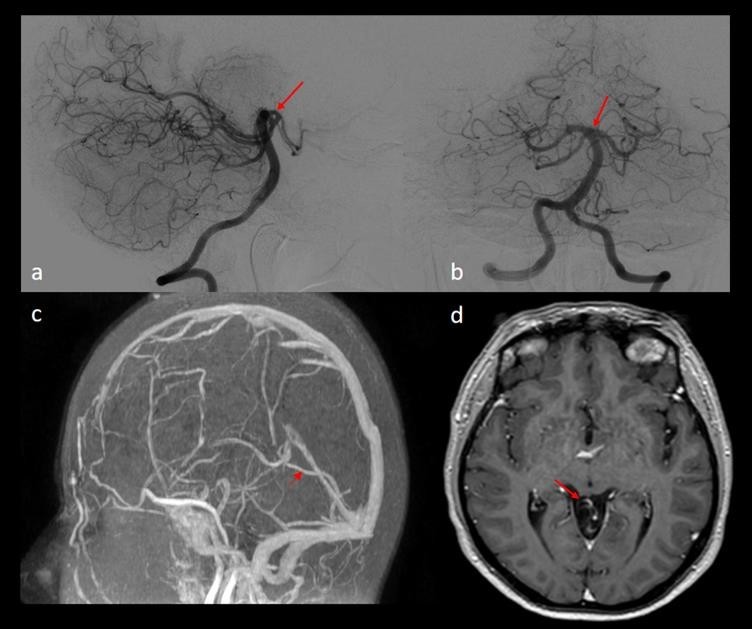

10 months later the patient, still asymptomatic, accepted to undergo a DSA. The DSA showed a complete resolution of the vein of Galen malformation with the absence of any signs of cerebral hemorrhage (Figure 3-a and 3-b). The follow-up cerebral MRI 6 months later confirmed the complete resolution of the vein of Galen malformation and a complete restoration of the arterial and venous cerebral circulation in this patient who remained intact on the neurologic examination (Figure 3-c and 3-d).

Figure 3- (a) Cerebral DSA lateral view showing normal vascular anatomy (red arrow) with complete thrombosis of the arteriovenous malformation. (b) Cerebral DSA anterior-posterior view showing a completely normal vascular anatomy (red arrow) and complete thrombosis of the arteriovenous malformation. (c) Cerebral MRI - TOF at 6 months follow-up post DSA showing no signs of arteriovenous malformation with normal vascular anatomy (red arrow showing a normal vein of Galen). (d) Cerebral MRI – T1W with gadolinium contrast showing the complete thrombosis of the vein of Galen malformation with normal vascular anatomy (red arrow).